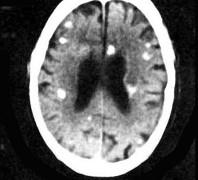

下列哪项有助于脑包虫病(如图所示)的诊断()A.有生食猪肉史B.皮下结节C.有食溪蟹史D.有疫水接触史E.有狗羊接触史

问题 下列哪项有助于脑包虫病(如图所示)的诊断()

选项 A.有生食猪肉史 B.皮下结节 C.有食溪蟹史 D.有疫水接触史 E.有狗羊接触史

答案 E